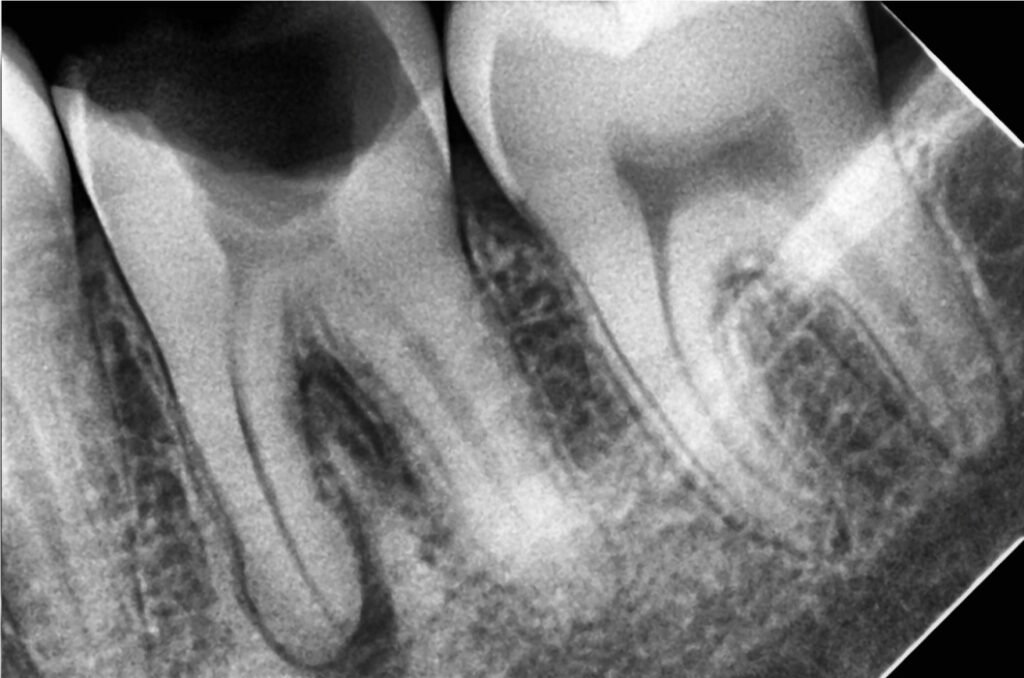

When the pulp gets infected due to decay, injury, or repeated dental procedures, it can lead to severe pain and eventually tooth loss if left untreated.

Causes of Pulp Infection

Several factors can lead to pulp damage or infection:

• Deep dental decay (cavities)

• Trauma to the tooth

• Cracks or chips

• Large fillings

• Repeated dental treatments on the same tooth